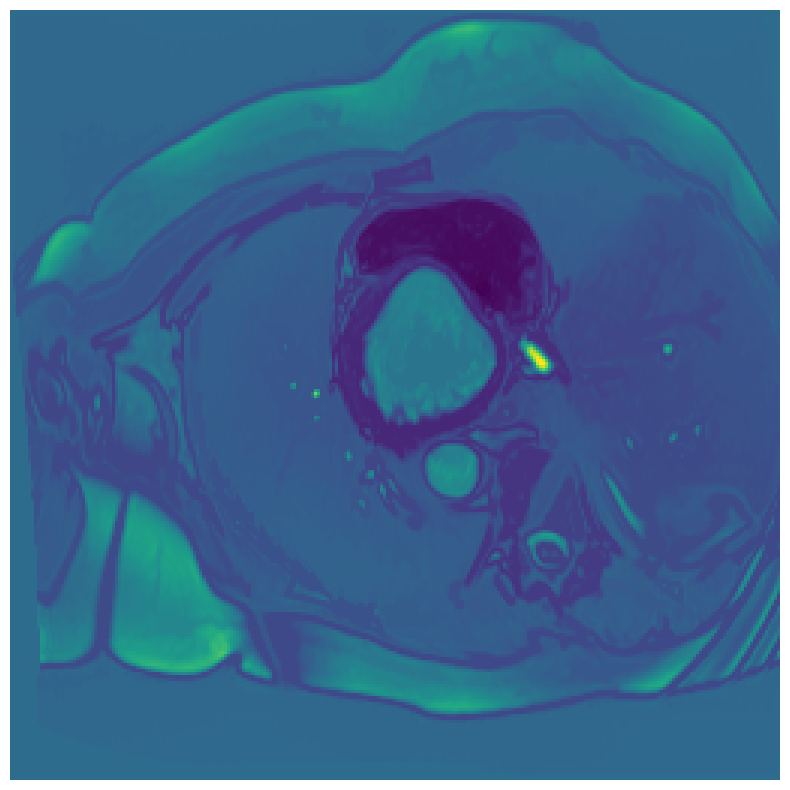

Generally, given an exact, full annotation of an object, such a Euclidean signed distance map encodes also information on the shape of an object. But when using a weak ground truth , where and , inferring a correct extent and shape of the objects is nontrivial. As shown in 1(b), Euclidean distance calculated from a point label source grows radially, regardless of the actual shape of the object, and thus makes little sense from an information point of view. Under the assumption of intra-object homogeneity and inter-object contrast (w.r.t intensities), this problem can be circumvented to a degree by using a distance function that takes also intensity values into account. An example of a commonly used distance measure with an intensity component is the Geodesic distance ([34]). Let denote a path between , with and being neighbors under a chosen adjacency relation. Reusing the notation from before, a Geodesic distance map from the boundary of the ground truth class , , can be defined as

Both the Intensity and the Minimum barrier distance are defined exclusively on the image intensity space. However, from the examples of distance map in 1(d), we can notice that the values still increase somewhat radially from the annotation. This behaviour is similar to the one of the Geodesic distance in 1(c) (which actually includes the spatial proximity in its definition), and is due to the summing operator in the general Geodesic distance definition in Equation 3. While the intensities of two neighboring pixels on a path may be the same, that will rarely be the case in real life, noise riddled images. This makes the Intensity distance function approximately monotonically increasing with increasing length of the path (in space), even on paths where the intensity is mildly fluctuating (e.g. consider a path with even pixels intensity value of and odd pixels intensity value of ). One could thus argue that such a definition of a distance, despite being based exclusively on intensities, is still capable of loosely encoding the spatial distance information.

On the other hand, while we can see that the MBD based maps are similar to Geodesic and Intensity ones (1(e)) with respect to the object shape recovery, they have a less pronounced and smooth increase in the values outward from the source point.

In contrast to Euclidean distance, the Geodesic, Intensity and Minimum barrier distance maps all encode contrast sensitivity and preserve the object structures by harnessing the intensity information of the underlying image. This holds even when calculated from point sources. In practice, using such maps for network training could mean a lower penalty for false positives that occur farther from the point annotation but are close to it in intensity. Thus still enabling the propagation of a sort of shape information (as it can be inferred from the raw image intensities).